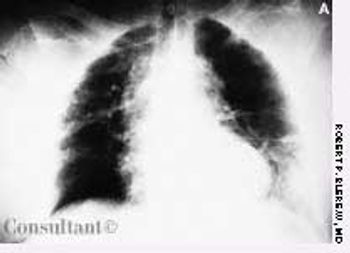

This rash, which covered a 68-year-old woman's body, was noted to have worsened during the past 2 months. A cephalosporin antibiotic had failed to clear the condition. The patient, a nursing home resident, suffered from emphysema, asthma, and heart disease. She had been receiving oxygen therapy and prednisone for 1 year.